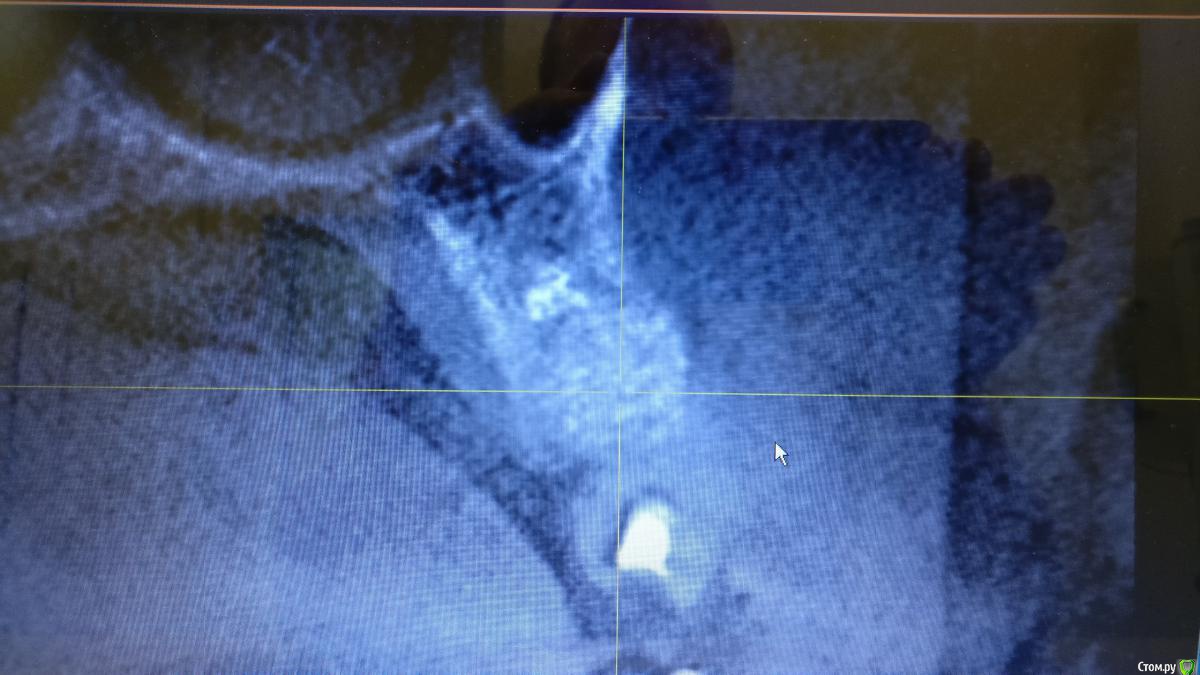

alboard Опубликовано 22 сентября, 2017 Поделиться Опубликовано 22 сентября, 2017 Что бы темы не плодить, спрашиваю тут. Было удаление 36го зуба в марте этого года. Удалял не я. Со слов пациента: после удаления в лунку засыпали БиоОсс. Кт свежее. Ожидать кашу? Ну и повторюсь, что в таком случае делать? Ссылка на комментарий

Павел7809 Опубликовано 21 октября, 2017 Поделиться Опубликовано 21 октября, 2017 Что бы темы не плодить, спрашиваю тут. Было удаление 36го зуба в марте этого года. Удалял не я. Со слов пациента: после удаления в лунку засыпали БиоОсс. Кт свежее. Ожидать кашу? Ну и повторюсь, что в таком случае делать?Ставьте спокойно 2 Ссылка на комментарий